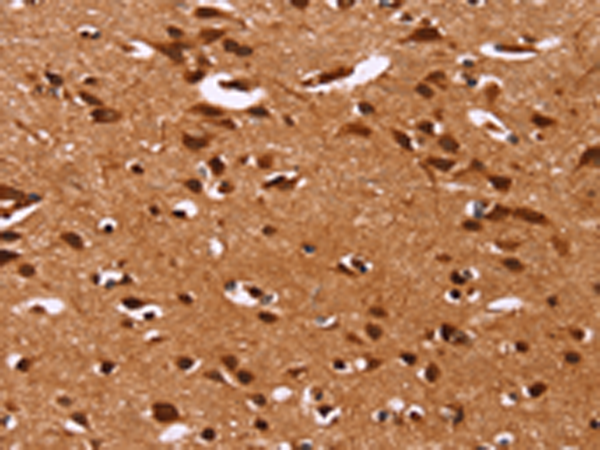

分类: 科研抗体货号: P11852别名: SYNI; SYN1a; SYN1b应用: WB,IHC反应种属: Human